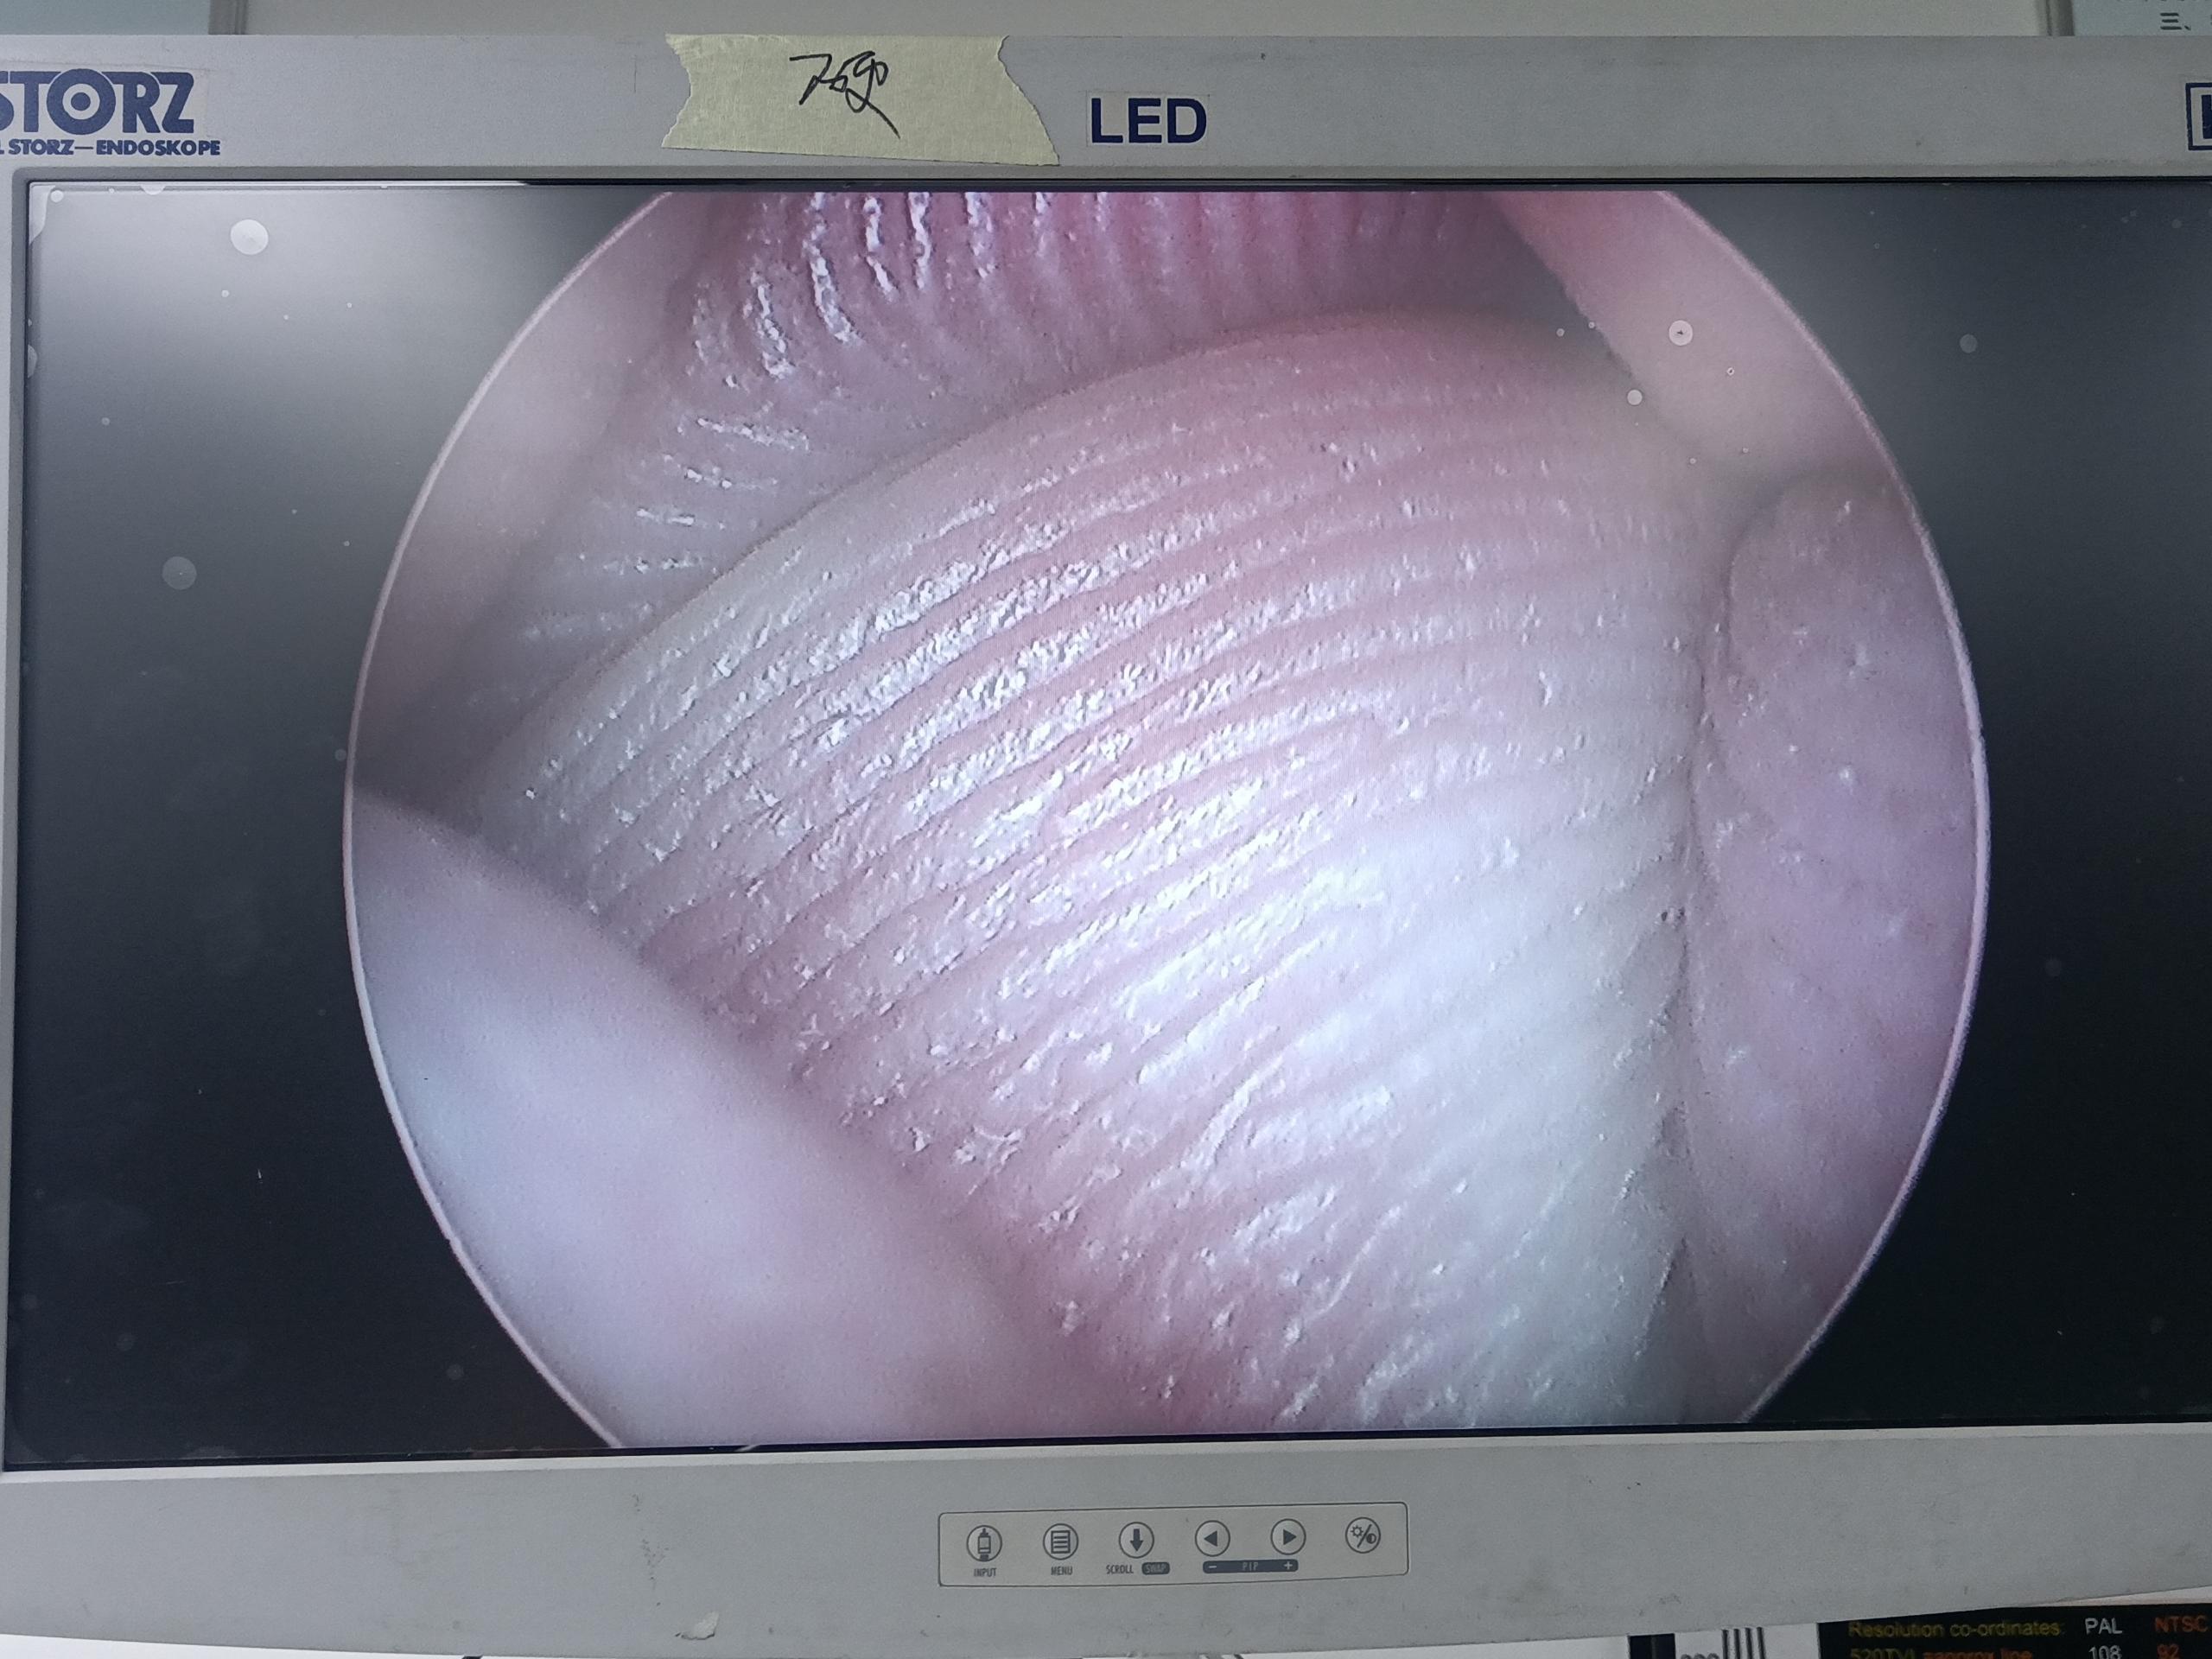

設(shè)備型號(hào)Wolf狼牌電切鏡8650.414

故障內(nèi)容圖像模糊,棒透鏡破碎,導(dǎo)光錐破碎,目鏡罩破碎,鏡身有磕碰,但不影響使用。

維修方案更換棒透鏡、導(dǎo)光錐、目鏡罩,校對(duì)圖像,內(nèi)窺鏡抗震蕩抗沖擊性能測(cè)試,內(nèi)窺鏡密封性性能檢測(cè);內(nèi)窺鏡抗震蕩性能測(cè)試,內(nèi)窺鏡冷熱沖擊性能檢測(cè)。